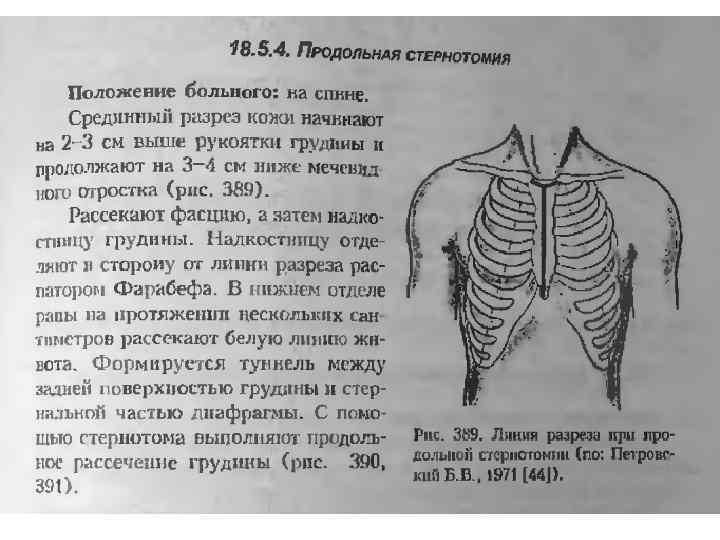

Аортокоронарное шунтирование • Техника. Продольная стернотомия (мягкие ткани послойно рассекают по срединной линии вдоль всей грудины) стернотомом. • Края грудины разводят расширителем.

Аортокоронарное шунтирование • Техника. Продольная стернотомия (мягкие ткани послойно рассекают по срединной линии вдоль всей грудины) стернотомом. • Края грудины разводят расширителем.